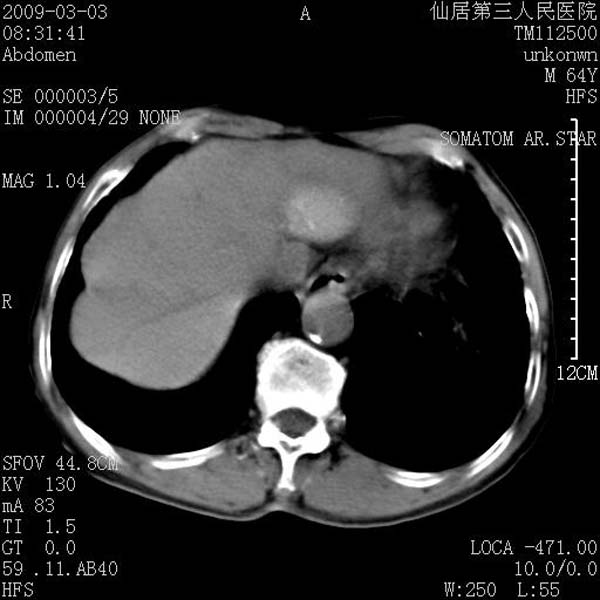

标题: CT18469:男性,64y,体检B超示肝脏低回声肿块,有胃溃疡手术 [打印本页]

患者,男性,64y,体检b超示肝脏低回声肿块,有胃溃疡手术史。

从平扫及增强的特点来看,支持肝脏腺瘤并出血。

支持肝脏腺瘤并出血。期待结果。

考虑肝静脉韧带裂区良性占位性病变(囊肿?)。

考虑肝囊肿并出血可能性大.